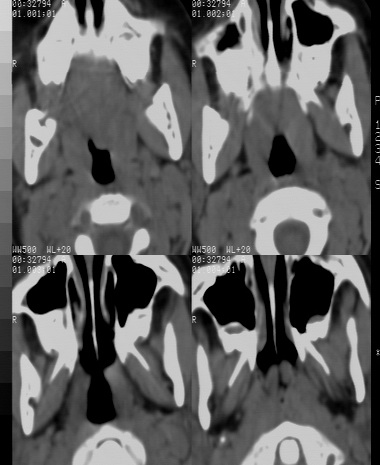

女 5岁 夜间打鼾数年 本人第一次遇到这样的病人,不知是不是鼻咽增殖体肥大?需不需要做手术,请同行给予指导。

鼻咽腔顶壁及后壁软组织明显肿胀,厚度约2.5cm,鼻咽腔气道轻度狭窄,加之临床病史,支持腺样体肥大。

结合病史的话,看到鼻烟后顶壁软组织增厚,应该考虑腺样体增大